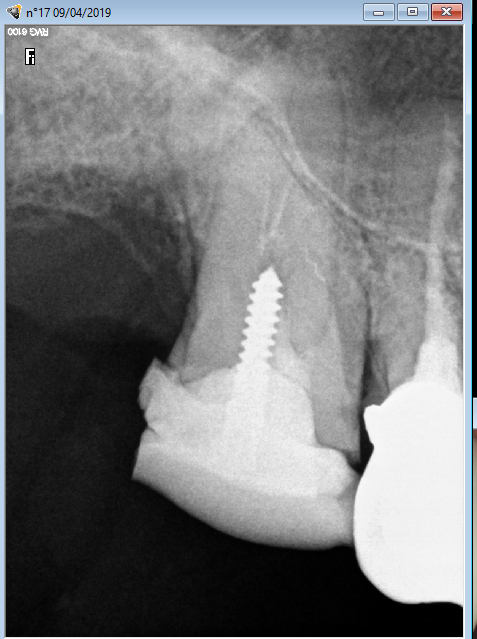

Rentable ? Scandaleux. La sécu n'a pas bien fait son travail. Il reste quelques petits morceaux de barbaque. -)))

Comme d'hab, tout dépend de quoi on parle... L'endo peut même être rentable au tarif conventionnel, sans acte npc ajoutés en sus :-)

Tout dépend de la qualité de réalisation de l'acte, du système ou des systèmes utilisés pour la préparation et l'obturation, etc...

Rentable. -)))